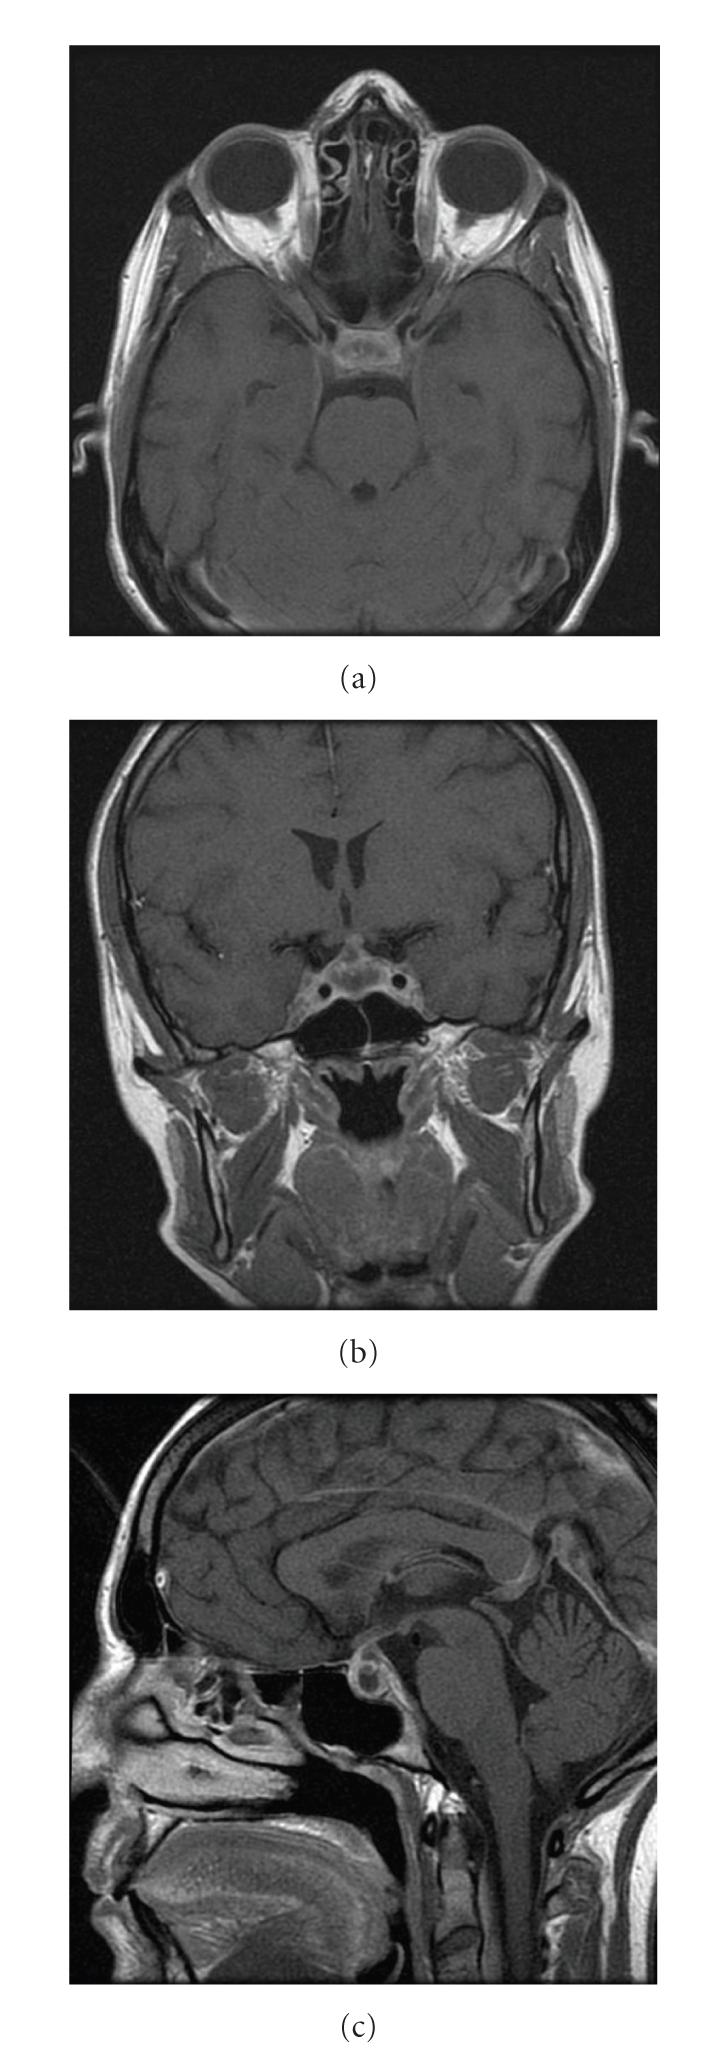

Background. Hypophysitis is an inflammatory disease of the pituitary gland that may mimic pituitary tumors clinically and radiologically. Case Description. We report a case of a xanthomatous hypophysitis initially diagnosed as pituitary adenoma. A 31-year-old woman presented with headache, diabetes insipidus, and amenorrhea. A head CT scan showed no intrasellar changes, while an MRI scan showed a sellar cystic mass. An endocrinological work up revealed mild hypocortisolism and diabetes insipidus (DI). Transsphenoidal surgery was performed. The intraoperative histological examination suggested a pituitary adenoma. The removed tissue showed central necrosis surrounded by accumulation of foamy cells and xanthomatous epithelioid cells. The patient made an uneventful postoperative recovery, Nevertheless, DI persisted and the adenohypophysis hypofunction did not recover. Conclusion. We describe an unusual inflammatory lesion of the pituitary gland mimicking an adenoma. A high level of clinical suspicion of inflammatory disorders is necessary for correct diagnosis and optimal management.